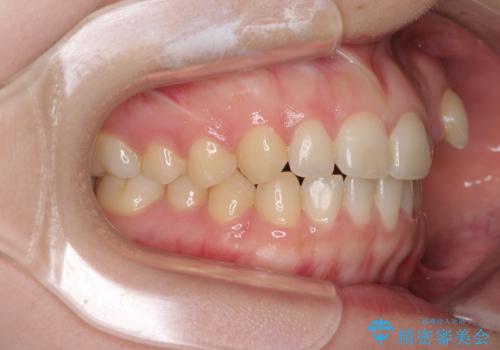

気になる残存乳歯と八重歯 ワイヤー矯正を併用したインビザライン治療

- 八重歯を気にして来院された患者様です。

八重歯のために乳歯が残存していたため、乳歯を抜去して八重歯となっている犬歯を歯列に収めることとしました。

八重歯の移動量が多くなるため、インビザラインと併用してワイヤー矯正を行い、八重歯を改善した後に、上下歯列をインビザラインで整えることとしました。

犬歯は歯根が長くて太いため移動に時間がかかる上に、周囲の歯が八重歯に寄ってきてしまうため、仕上がるまでに期間がかかりました。